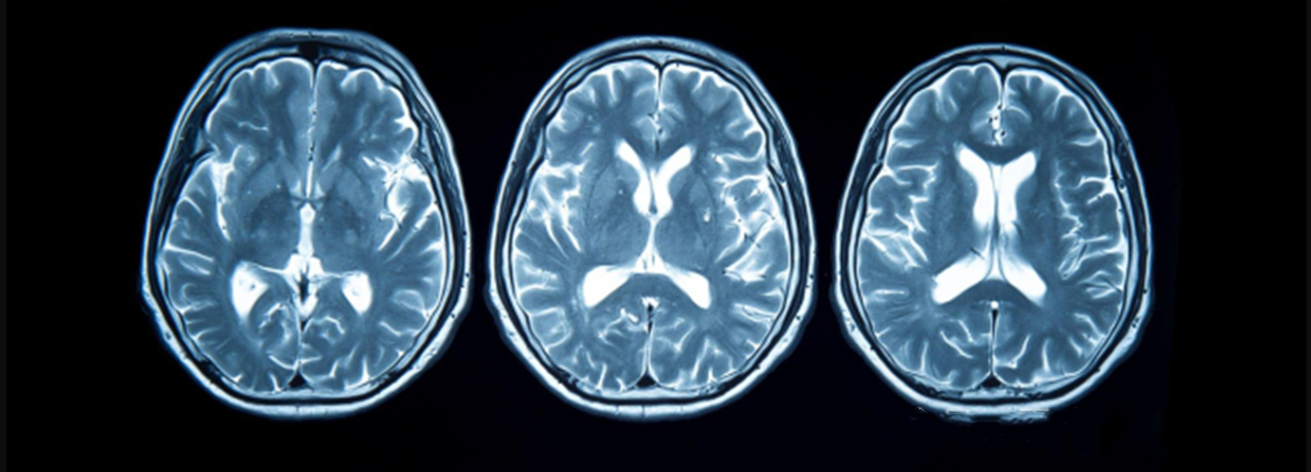

創(chuàng)傷性腦損傷(TBI)是一種由外力導(dǎo)致的腦部損傷及功能障礙,是一種異質(zhì)性疾病。在多重機(jī)制作用下,TBI患者的致殘率和病死率較高,給家庭和社會帶來沉重負(fù)擔(dān)。TBI的臨床治療多以外科手術(shù)及減輕腦缺氧、腦水腫和代謝紊亂等對癥治療為主。近年來,干細(xì)胞逐漸成為TBI治療的研究熱點(diǎn)之一。

創(chuàng)傷性腦損傷(TBI)是全球范圍內(nèi)創(chuàng)傷相關(guān)損傷中導(dǎo)致死亡和殘疾的最大因素。全球各種原因、各種嚴(yán)重程度的TBI發(fā)病率估計(jì)為每年6900萬例。急性臨床護(hù)理的進(jìn)步提高了創(chuàng)傷性腦損傷后的存活率,但目前尚無批準(zhǔn)的TBI治療方法,致使許多患者終身殘疾。

圖片:來源于網(wǎng)絡(luò)